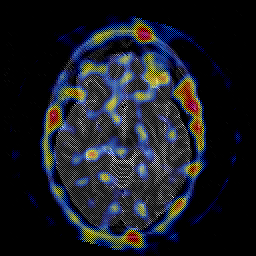

Glioblastoma multiforme overlay -- Slice #24

[Home][Help][Clinical][Tour 1][Tour 2][Tour 3] Slice 24